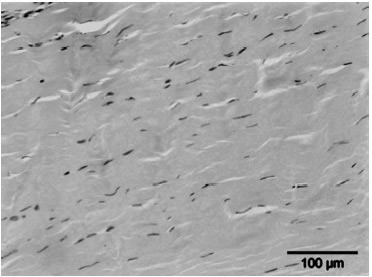

- Het stimuleren van de collageenproductie en het afvoeren van beschadigd collageen, wat resulteert in een verhoogde matrix-turnover.

- Het beïnvloeden van stamcelmigratie en -proliferatie via mechanotransductie.

- De stijging in de celpermeabiliteit. De stimulatie van de celdeling.